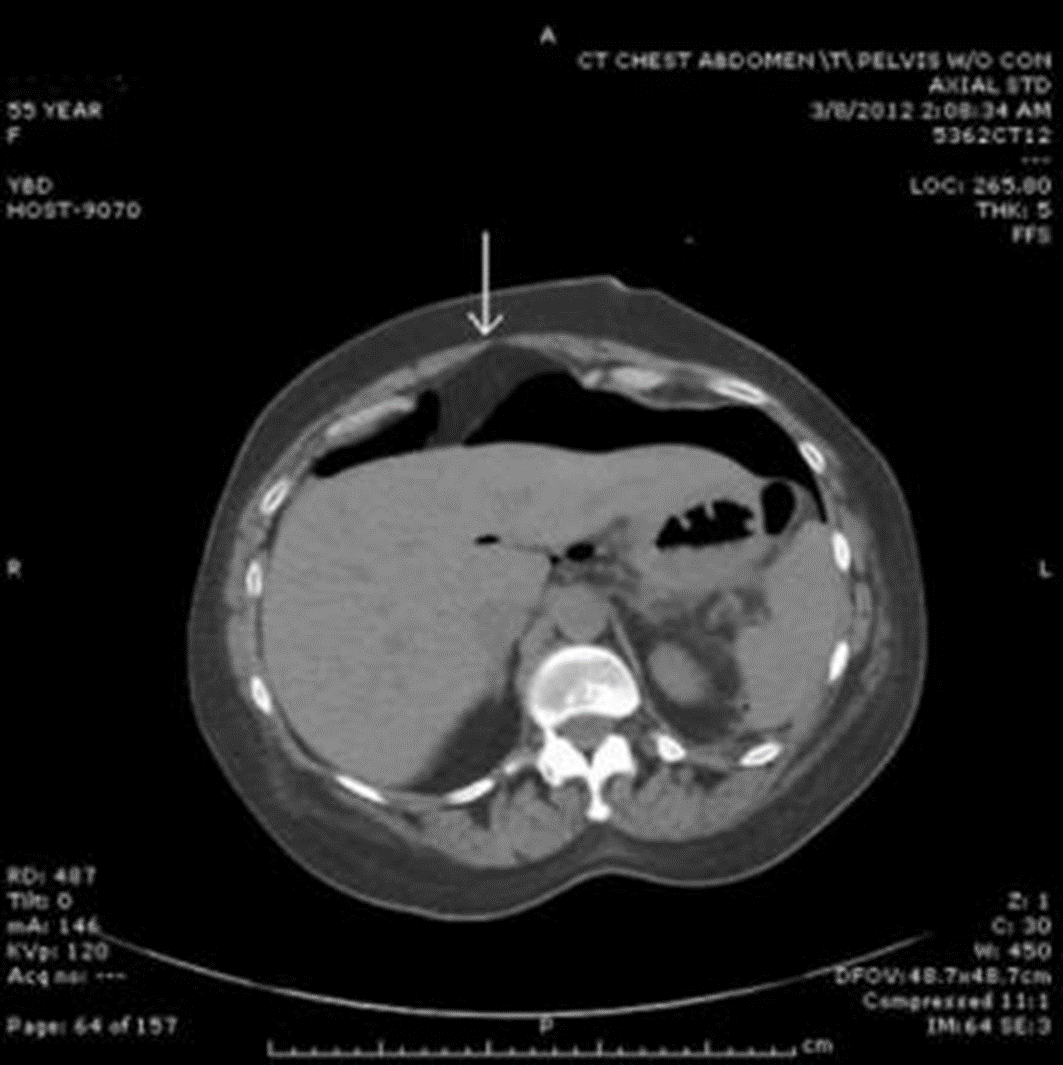

CT với khí tự do ổ bụng

image 4

Một vết loét dạ dày có thể xâm nhập vào thành dạ dày. Nếu được khu trú lại để ngăn sự rò rỉ vào khoang phúc mạc, tránh sự xâm nhập tự do thì gọi là thủng bít. Tuy nhiên, loét có thể xâm nhập vào tá tràng và vào khoang nhỏ liền kề (mạc nối nhỏ) hoặc cơ quan khác (ví dụ như tụy, gan). Đau có thể rất dữ dội, dai dẳng, ở các vị trí khác ngoài bụng (thường là lưng khi thủng ổ loét sau tá tràng vào tụy) và thay đổi theo tư thế. CT hoặc MRI thường cần để xác định chẩn đoán. Khi điều trị mà không lành thì cần được phẫu thuật.

Cần phẫu thuật ngay. Trì hoãn càng lâu thì tiên lượng càng kém. Kháng sinh đường tĩnh mạch có tác dụng chống lại vi khuẩn đường ruột (ví dụ như cefotetan, hoặc amikacin và clindamycin). Thông thường, bệnh nhân được đặt sonde dạ dày để hút dịch liên tục. Trong số ít trường hợp phẫu thuật không thể thực hiện được thì tiên lượng kém.